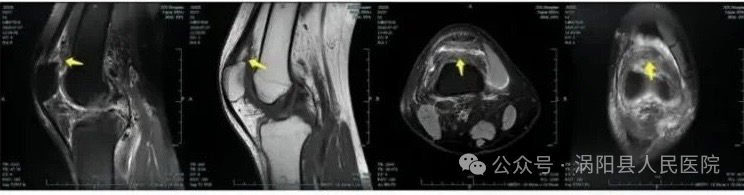

下图为体位固定和放射治疗计划。